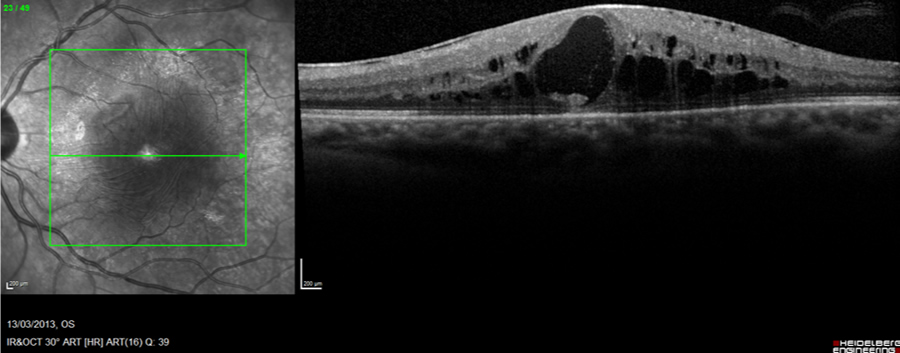

Figure 1: Diabetic retinal edema due to macular traction (pre-diabetic retinopathy surgery)